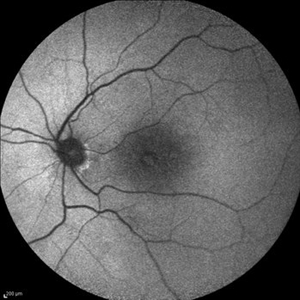

Behcet's Disease Behcet's DiseaseMar 13 2013 by Hamid Ahmadieh, MD Infrared image of the right eye of a 23-year-old man with retinal vasculitis and branch retinal vein occlusion (BRVO) due to Behcet's disease . Photographer: Solmaz Shahmohammad, Negah Eye Center, Tehran Imaging device: Heidelberg Spectralis Condition/keywords: branch retinal vein occlusion (BRVO), infrared image, retinal vasculitis